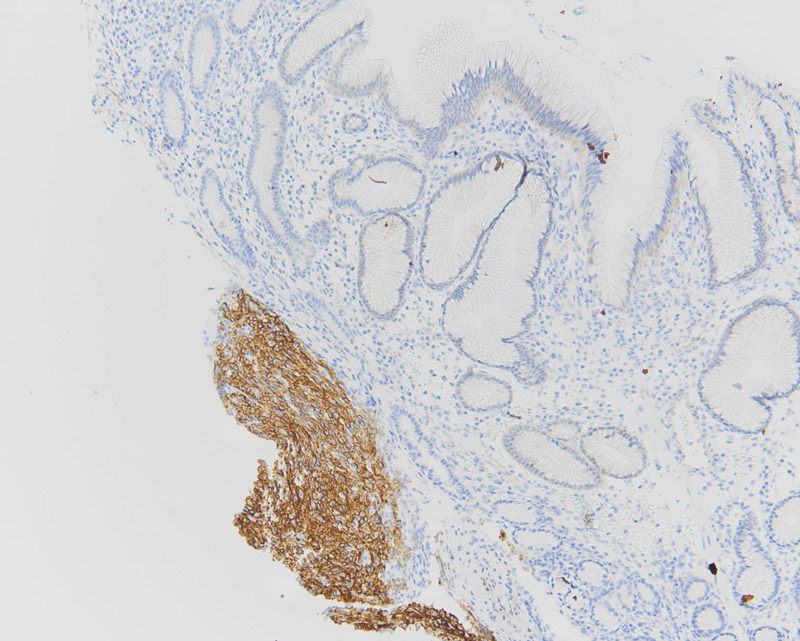

Initial laboratory work up demonstrated that the patient was anemic (Hgb = 4.5 g/dL), with WBC and platelet count within normal limits. CT scan revealed two exophytic masses originating from the greater curvature of the stomach at the antrum with intra and extraluminal components (Figure 1). Upper endoscopy noted a few small, smooth sessile polyps in the gastric antrum. One large ulcerated polyp was noted close to the pylorus.

The polyp was non-obstructing and not actively bleeding; biopsies were taken of this polyp. Histologically the biopsy specimen demonstrated a proliferation of uniform mixed epithelioid and spindle-epithelioid cells amongst antral-type mucosa (Figures 2, 3). No significant pleomorphism or mitotic figures were identified. Immunohistochemical stains for DOG1 and c-Kit (CD117) were positive (Figures 4 and 5, respectively). A subsequent wedge resection of the stomach to include the lesions was performed and confirmed the original biopsy diagnosis (Figure 6). Molecular testing for c-Kit and PDGFRA were performed and were negative.